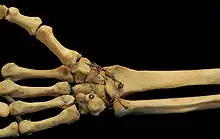

Ligamentos

Estas cuatro articulaciones de la CMC están sostenidas por ligamentos transversales fuertes y longitudinales más débiles: los ligamentos carpometacarpianos dorsales y los ligamentos carpometacarpianos volares o palmares.[7]

Los ligamentos interóseos están formados por fibras cortas y gruesas, y se limitan a una parte de la articulación carpometacarpiana; conectan los ángulos inferiores contiguos del capitado y el hamate con las superficies adyacentes del tercer y cuarto hueso metacarpiano.

La descripción del número y los nombres de los ligamentos de la primera CMC varía considerablemente en la literatura anatómica.Imaeda et al., 1993 describen tres ligamentos intracapsulares y dos extracapsulares como los más importantes para estabilizar el pulgar:[1]